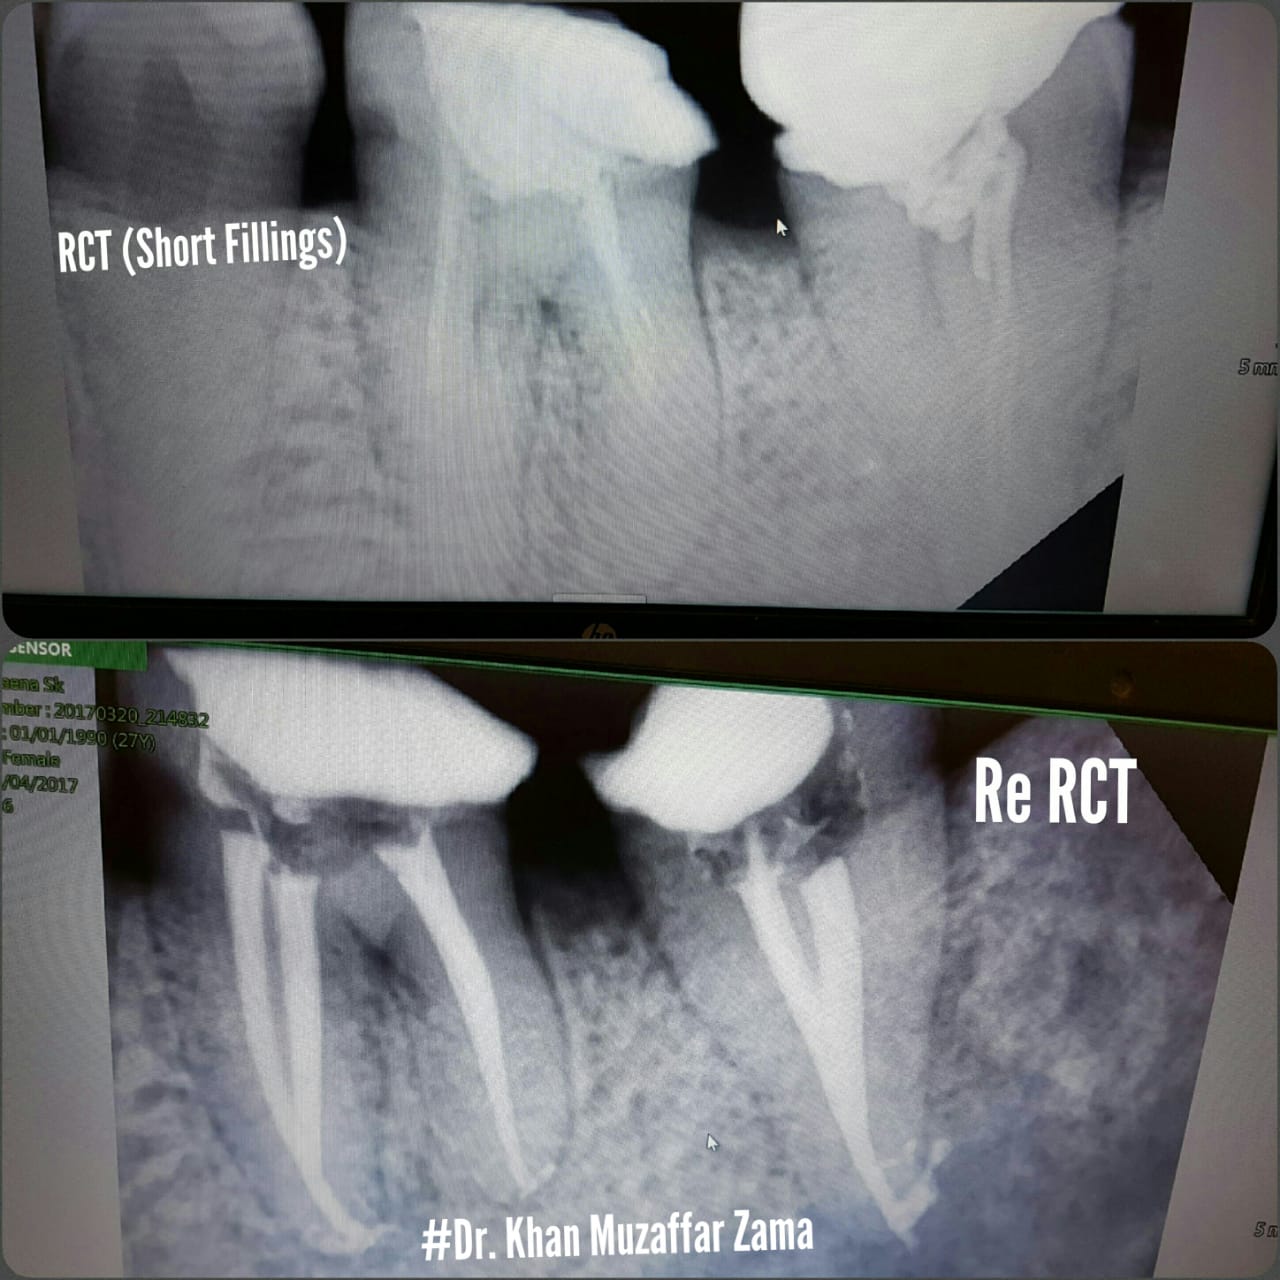

Cases